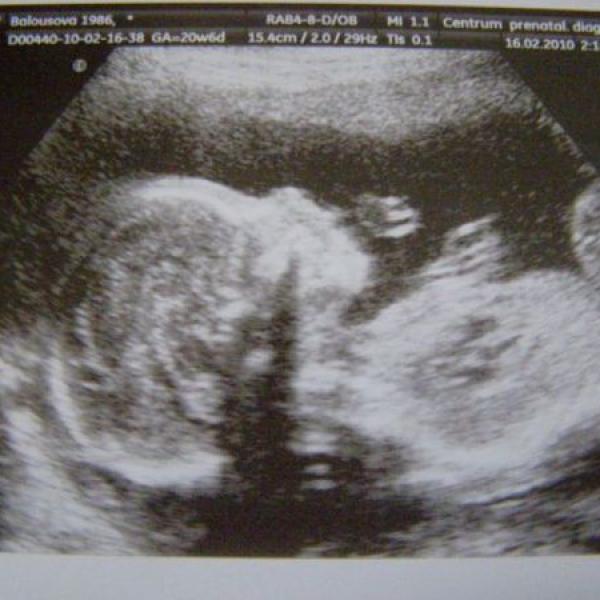

ahoj maminky, tak dneska jsme byli s tatínkem na velkém ultrazvuku.oba jsme nadšení,hlavně já,protože vím co to bude,tatínek se chce nechat překvapit,ale tajně si přeje holčičku a to př